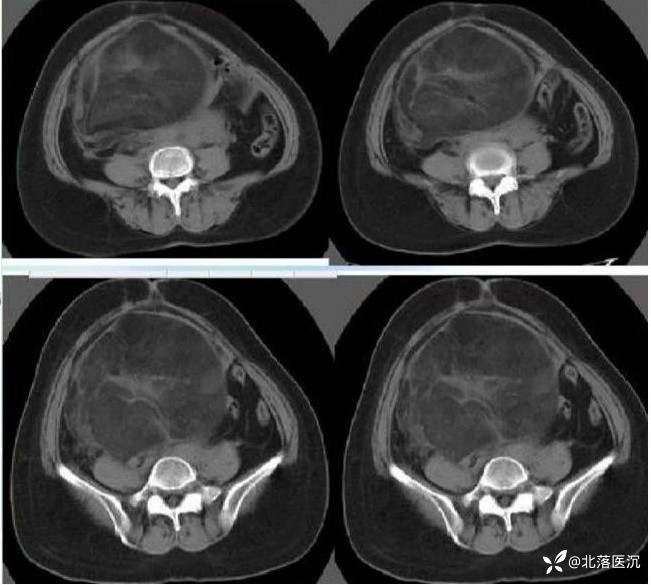

双侧附件区可见巨大囊性包块影,最大截面大小约203X119mm,98x95mm,囊液密度均匀,未见明显分隔,病变左侧可见斑片状脂肪密度影及结节状钙化影,边界清楚,下方小病变内见脂液平面,周围肠管及子宫受压移位。腹膜后主动脉旁及升结肠周围脂肪间隙内见多发肿大淋巴结,较大者短径约10mm。

1、双侧附件区占位,考虑囊性畸胎瘤可能,畸胎瘤继发浆液性囊腺瘤待除外,建议MRI增强检查;

病理学诊断:成熟性囊性畸胎瘤